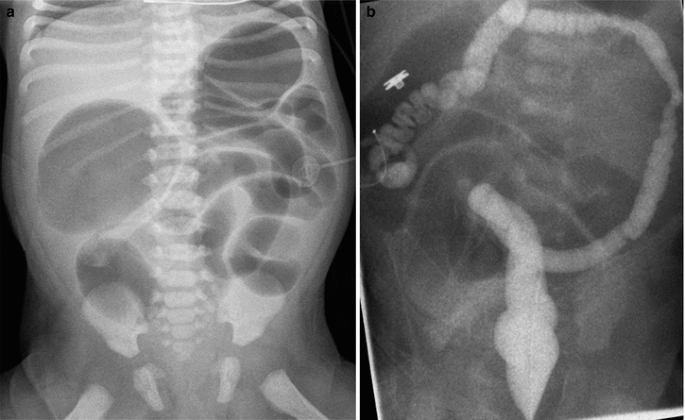

Pediatric Gastrointestinal Radiology

- Choledochal Cyst